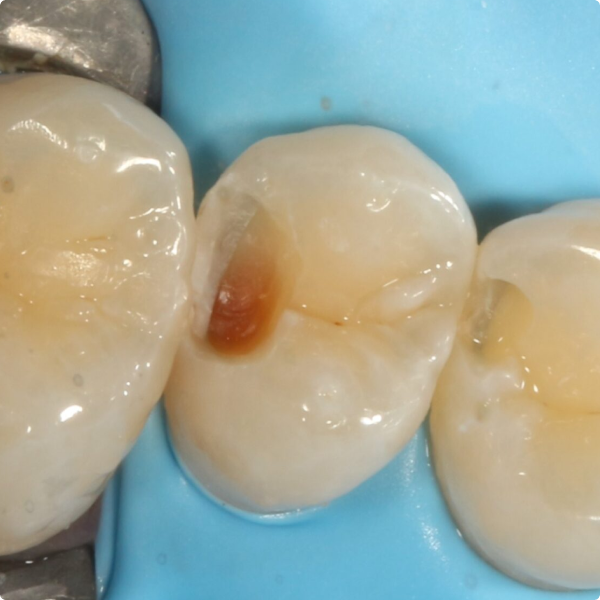

When a 17-year-old patient arrived for a routine six-month check at Dr Kiran Shankla’s practice, there were no complaints or concerns raised by the patient. During the examination a subtle colour change was observed on the upper left premolar. A bite-wing X-ray revealed a cavity, further confirmed with the aid of software.

Although Stela can be used without a rubber-dam, Dr Shankla opted for one to maintain optimal isolation and control. After removing the decayed tissue, photographs were taken to document the cavity’s extent. A sectional matrix was placed to ensure proper contact, given the size of the lesion, then the Stela system was applied.